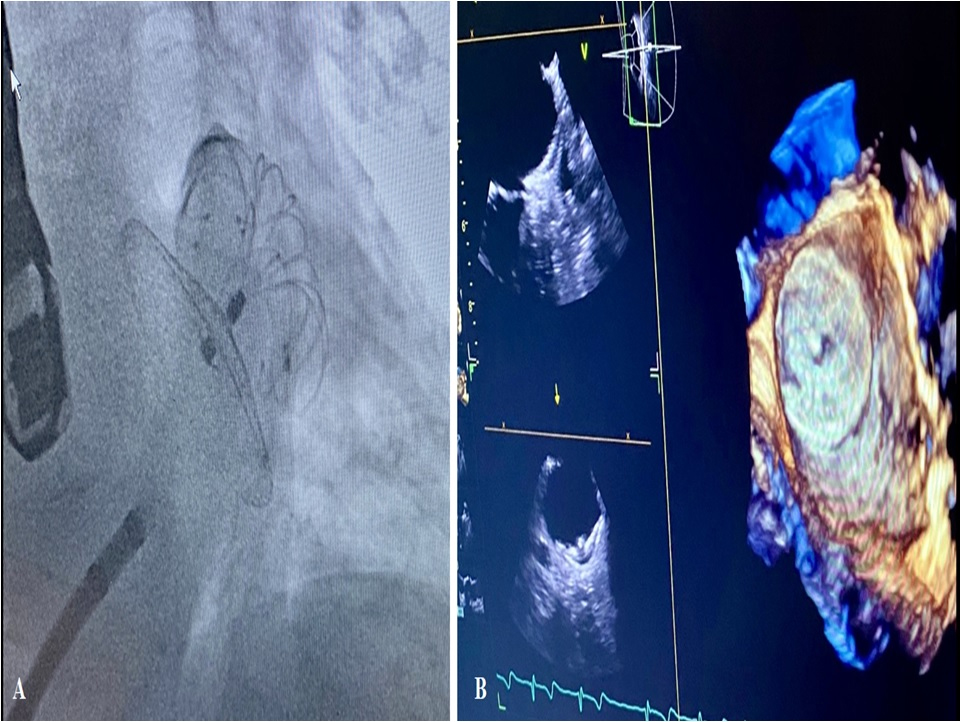

During percutaneous LAAO and TEE monitoring it is necessary that an expert operator accurately identifies the projections useful for a generic re-evaluation at the beginning of the procedure, for the transseptal puncture, for the correct sizing and for the correct positioning of the device (Fig. 1).

Fig. 1.TEE monitoring during percutaneous LAAO with Watchman Flex device. (A) Highlights the transseptal puncture maneuver. (B) Describe device positioning with double curve sheath. (C,D) Highlights in 2 D and 3 D TEE modality the complete occlusion of LAA.